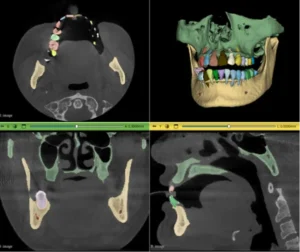

The crux of converting raw DICOM images into a surgically useful AI is medical image segmentation. This is where raw pixels transformed into anatomical reality.

For surgical planning AI, accurate segmentation not a luxury; it is the fundamental prerequisite. If an AI is tasked with delineating a tumor for resection, a 2 mm error in boundary definition could lead to incomplete resection (endangering the patient) or excessive tissue loss (resulting in functional deficit).

This phase is where “sandbox” experimentation meets the rigors of clinical necessity. The AI is trained to understand complex anatomy with high precision, building the “map” that will guide the surgeon.